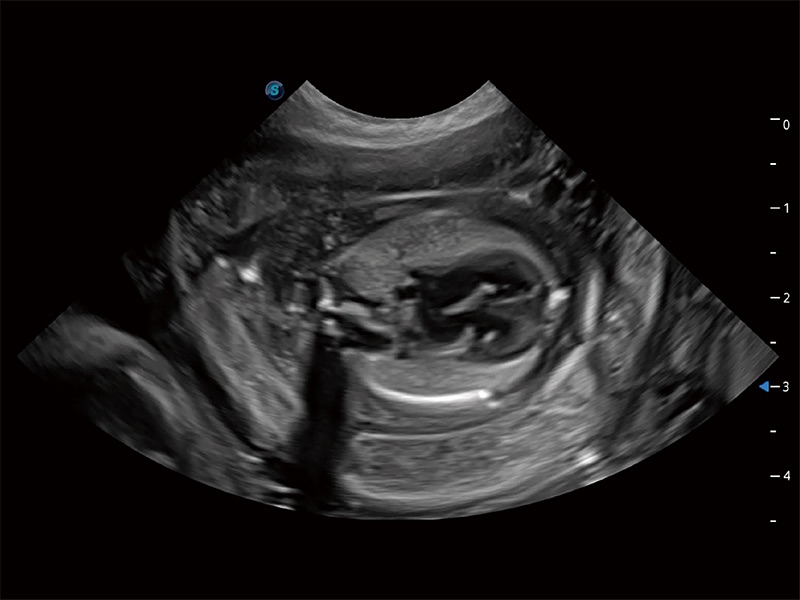

ProPet 80 专为动物医生设计,对不同的动物体型和生理结构作出了针对性的优化。通过动物影像专用软件,可满足个性化的应用需求,帮助动物医生获得更精确的诊断数据。

为精细结构及组织边缘提供高清晰度的图像和更大的成像视野。帮助减轻医生的用眼疲劳,快速精准获得测量的数据。

ProPet 80 全新的动物超声智能软件和丰富的探头群,为动物医生提供了高清晰度和精细分辨率的图像,无论在宠物、马科、畜牧还是实验室动物等应用中都可以轻松应对,为您的日常工作带来满意的体验。